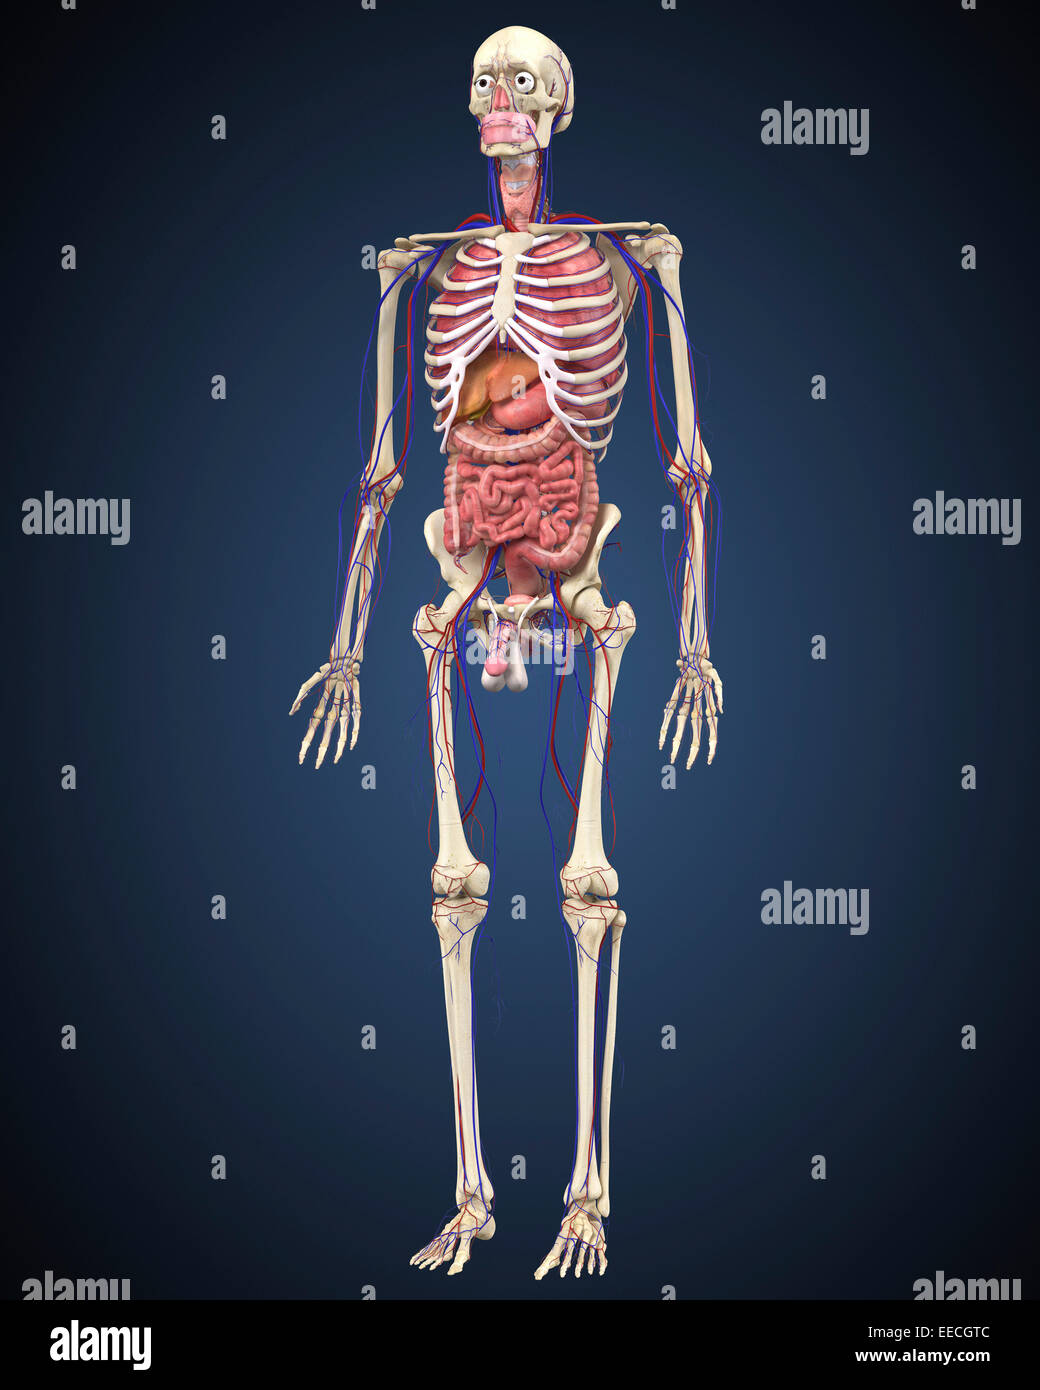

Human skeleton with organs and circulatory system. Stock Photohttps://www.alamy.com/image-license-details/?v=1https://www.alamy.com/stock-photo-human-skeleton-with-organs-and-circulatory-system-77723308.html

Human skeleton with organs and circulatory system. Stock Photohttps://www.alamy.com/image-license-details/?v=1https://www.alamy.com/stock-photo-human-skeleton-with-organs-and-circulatory-system-77723308.htmlRFEECGTC–Human skeleton with organs and circulatory system.